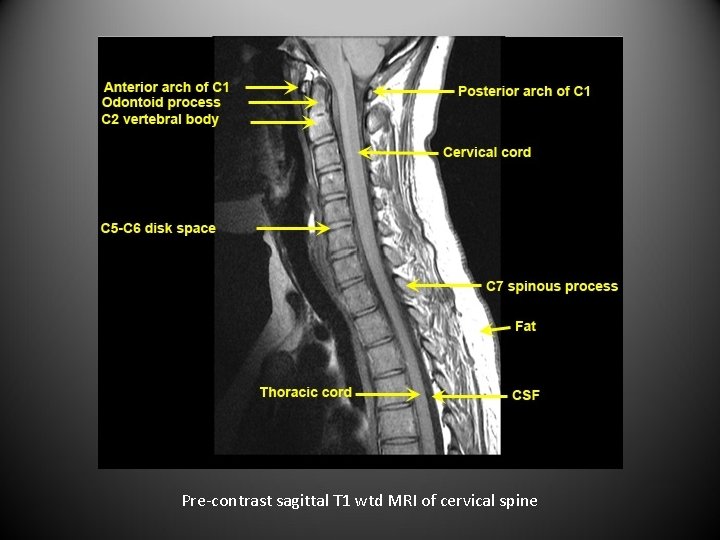

Spinal cord anatomy

Pre-contrast sagittal T 1 wtd MRI of cervical spine